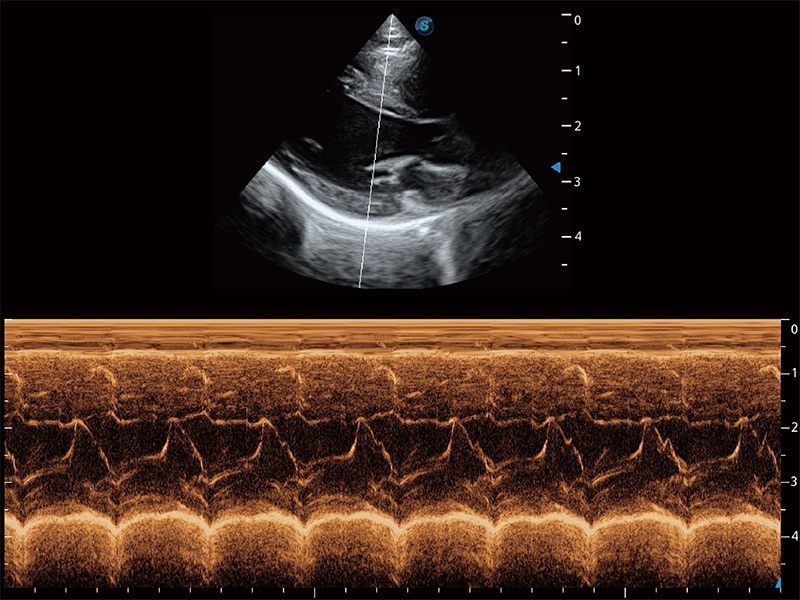

ProPet 80 配备了丰富的心脏探头群、先进的成像技术和专业的心脏测量工具,可帮助动物医生为不同体型和生理结构的动物提供心脏和心肌功能的全面评估。

通过360度任意调节3条M型取样线,在同一心动周期上观察心脏不同位置的运动曲线,得到准确的心功能测量数据,有效评估心肌运动及左心室功能。

能够基于左心室壁追踪和辛普森法,自动计算射血分数,支持多个可移动点描迹,与手动测量相比,极大节省了动物医生的时间和精力。